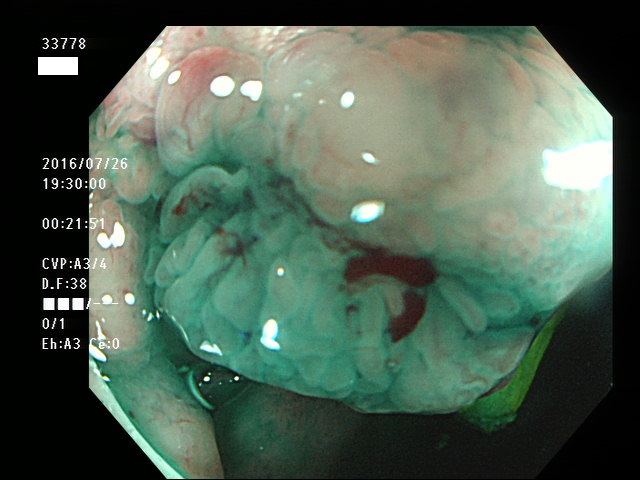

回盲弁(小腸と盲腸の境界)や、憩室の中、炎症で腫れた部位などは複雑に凸凹しており、ここに微小な病変、平坦な病変があると認識が困難になり見落としの危険が高くなります

| 憩室内に発生した腺腫 | 憩室内に発生した腺腫 |